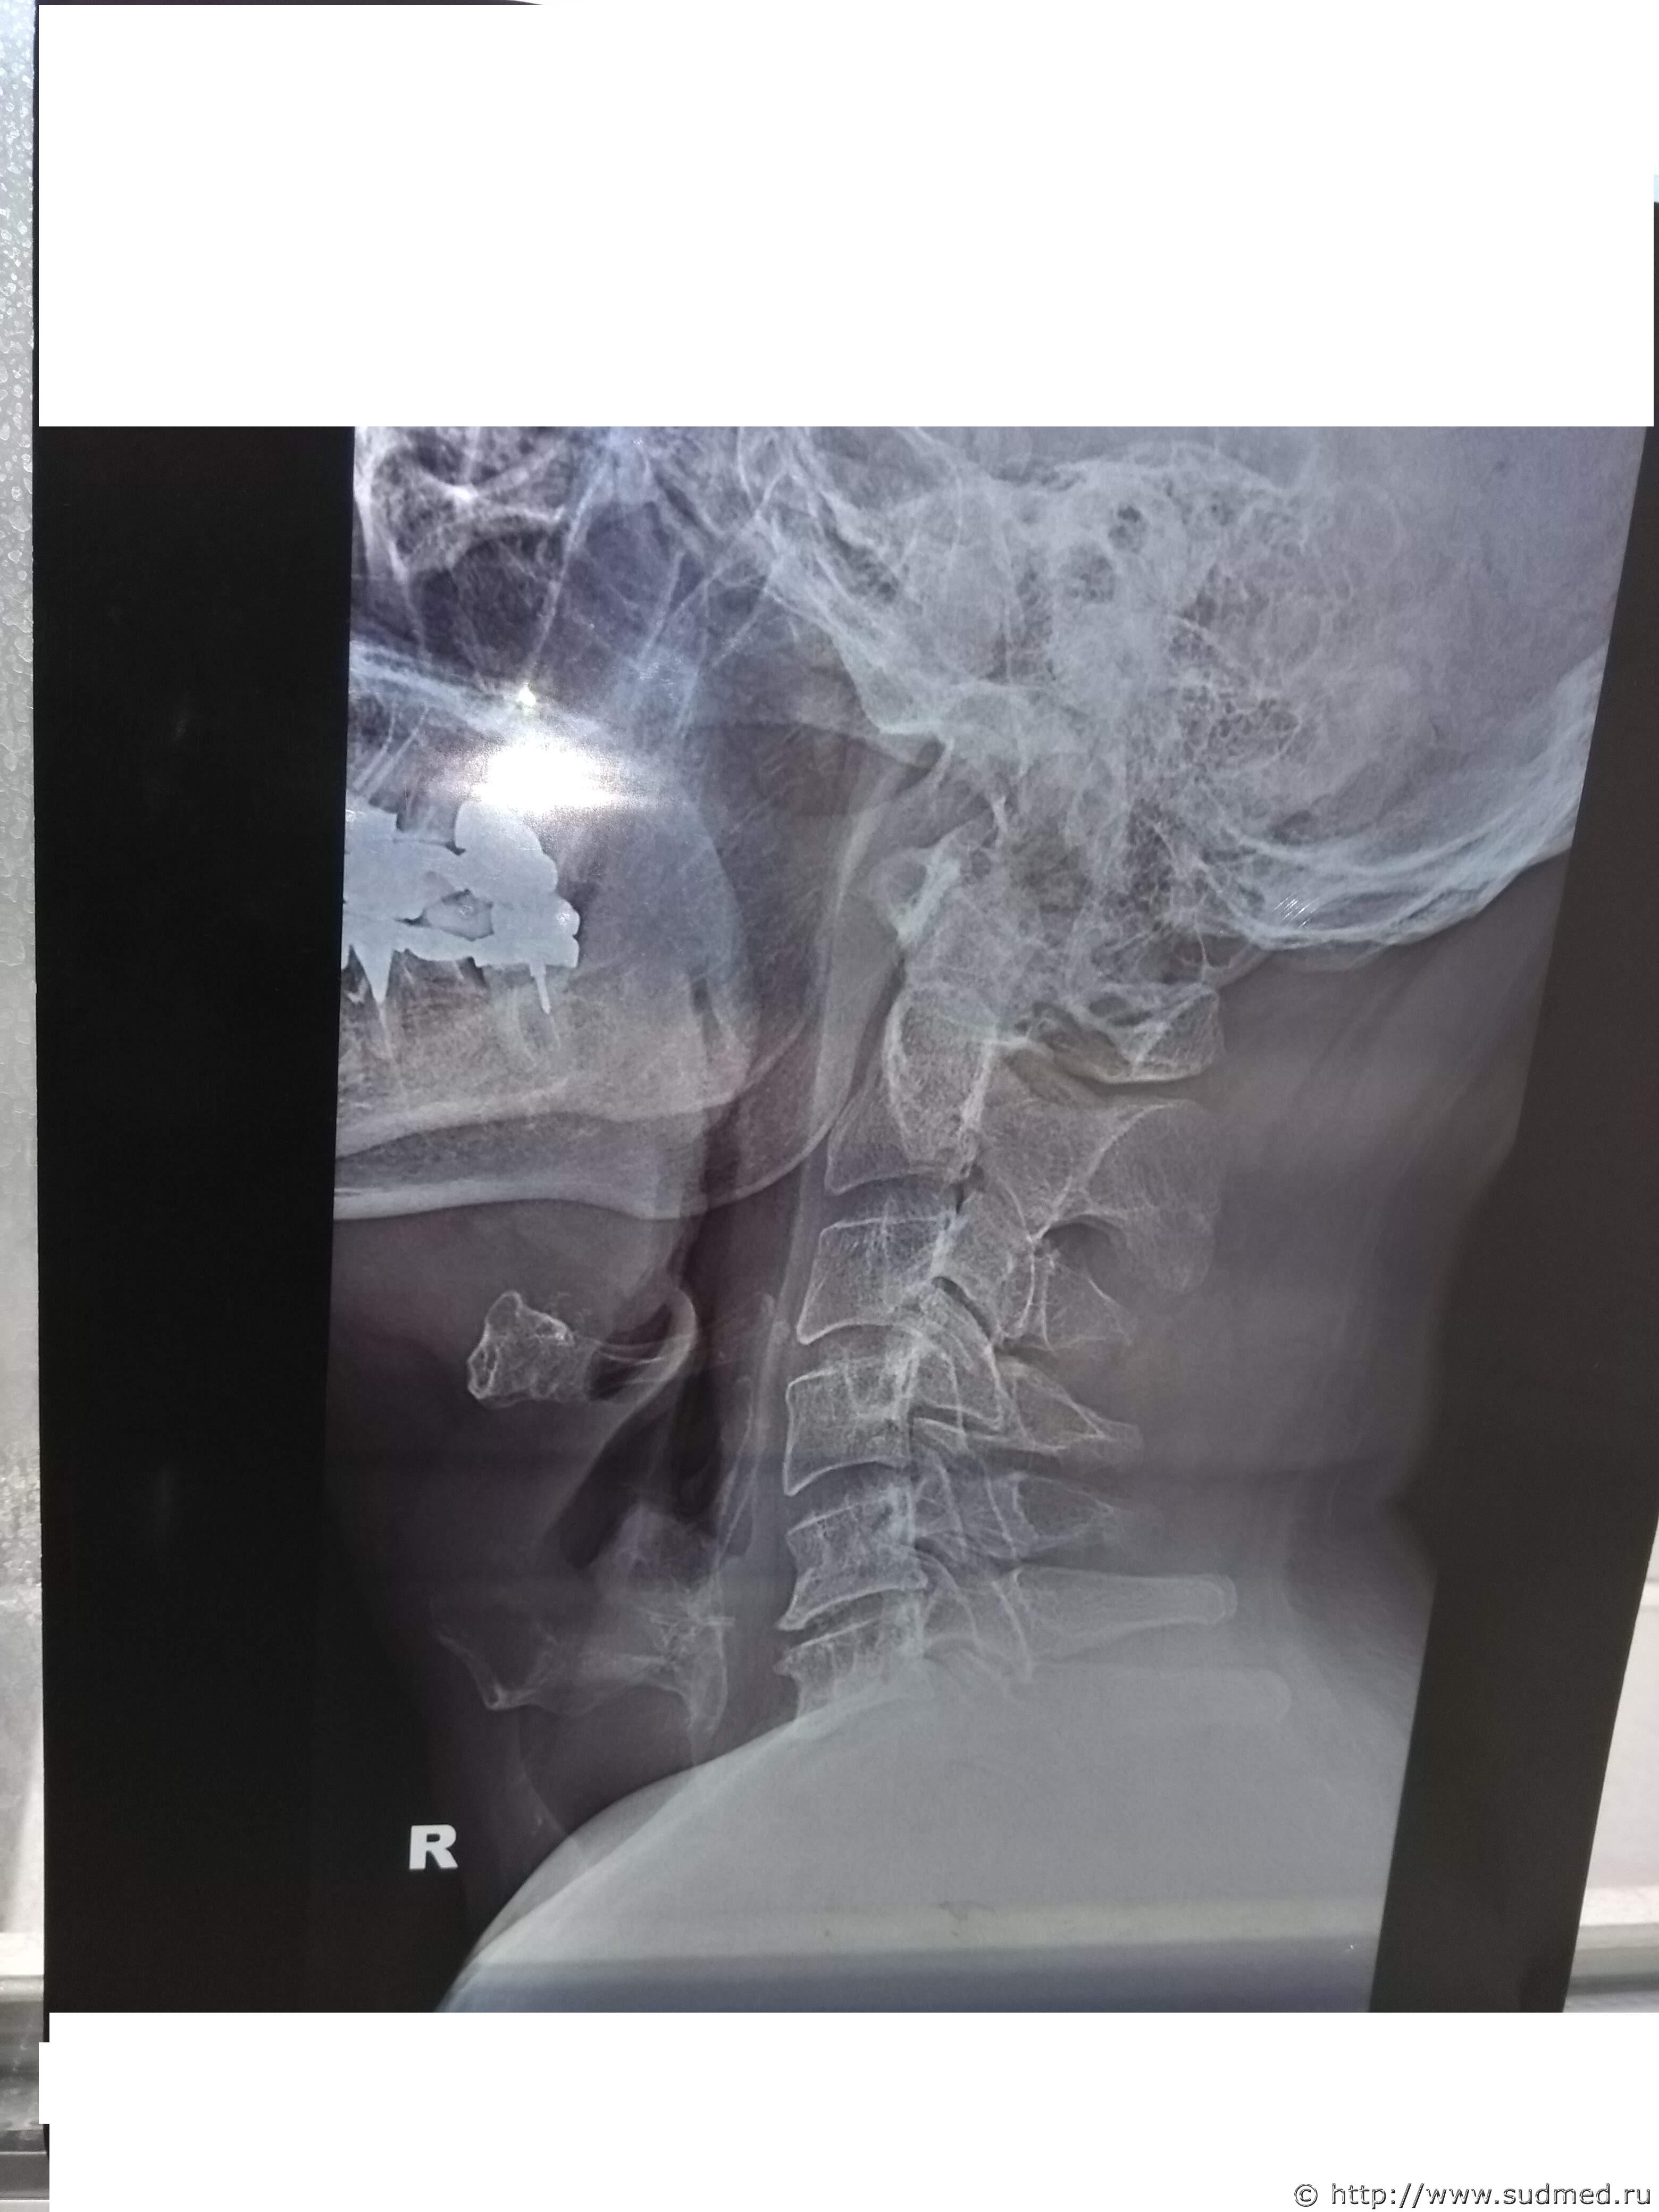

Какие повреждения видны на этой фототаблице?

Похоже на перелом щитовидного хряща, но утверждать не берусь: качество изображений низкое.

6. Правильно писали. Стандартные рентгенограммы шейного отдела позвоночника практически не показывают хрящей шеи. Для такого исследования нужны специально и тщательно подобранные условия рентгеновского исследования. В абсолютном большинстве случаев в лечебных учреждениях этим "не заморачиваются". МРТ, КТ, УЗИ (убывание в плане информативности) лучше, чем "обычные" рентгенограммы шейного отдела позвоночника, рутинно выполняемые в больнице или поликлинике. (Идеальные условия для исследования хрящей гортани нам предоставляет труп - есть возможность непосредственно изучить их, в т.ч. с увеличением, проследить и проанализировать каждое повреждение, в т.ч. четко определить "старое" оно или "свежее").

1. Рентгенограммы бывают разные. В первую очередь это зависит от условий съемки. Обычная цель съемки области шеи - исследование состояния шейных позвонков. В таком случае мягкие и хрящевые ткани шеи - помеха для визуализации костных структур. Маскирующее влияние этой помехи устраняется соответствующими параметрами рентгеновского исследования. Рентгеновское исследование хрящей гортани - отдельная и не очень простая задача лучевой диагностики. Не стоящая "на потоке" в лечебных учреждениях. В Вашем случае такие рентгенограммы сделаны.

Между тем врач рентгенолог на суде сказал:

1. Снимок сделан для исследования костных структур шеи. Объясняется тем, что в центре снимка находится позвоночник, а не гортань. У рентгеновского аппарата два режима, один для исследования костных структур, второй для исследования мягких тканей.

2. На рентгеновском снимке не видно щитовидного хряща. Т.е. получается как в одном фильме. Ты суслика видишь. Нет. А он здесь есть.